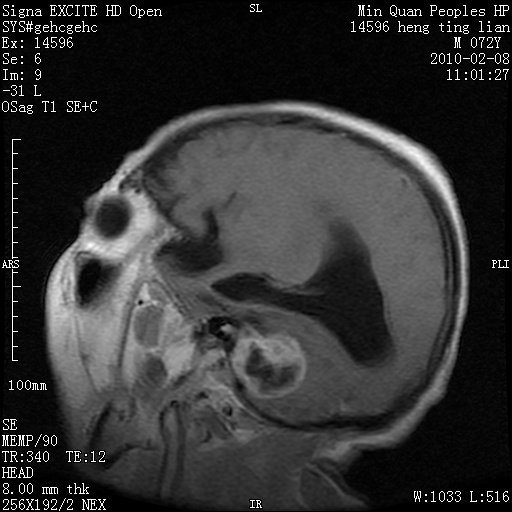

m,72,头疼,头晕两年,伴视力模糊三月,饮食呛咳两天。pe:颈部抵抗,左眼突出,左眼瞳孔约3mm,对光反射消失,双眼失明,伸舌困难,双肺呼吸音粗,心率110次/分,左上肢肌力i级,左下肢屈曲,肌张力高。现有08年2月19mri平扫及10年2月8日mri增强请会诊。ct病灶呈低密度伴散在点、片状等密度区,无明确钙化(无ct片资料可供上传)。[

脑外肿瘤,囊实性,环状不规则强化,内听道扩大,考虑神经源性肿瘤

左侧桥小脑区占位伴梗阻性脑积水----考虑 1神经鞘瘤 2室管膜瘤。

左侧桥小脑区神经鞘瘤伴梗阻性脑积水。

脑外肿瘤,病灶呈匍匐蔓延,表皮样囊肿可能性大。